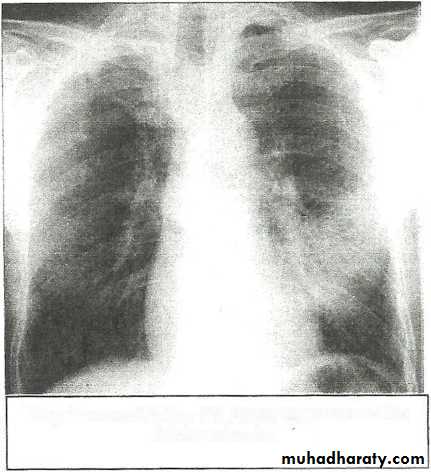

Massive pleural effusion with mediastinal shift to the left.

(A) Chest radiograph(B) CT coronal reconstruction. A massive effusion displaces the mediastinum to the left. CT shows the important pleural effusion together with the enhanced atelectatic left lung.

Note also the depression of the right hemidiaphragm (arrows).